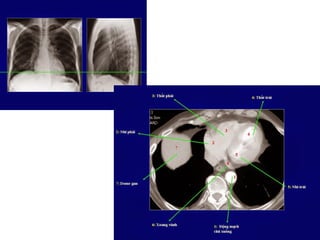

• Axial: ngang,Sagittal: đứng dọc,Coronal: đứngngang

CT NGỰC

CỬASỔ:

1. T

rungthất/mômềm(mediastinalwindows)

2. Phổi (lungwindows)

3. Xương (bonewindows)